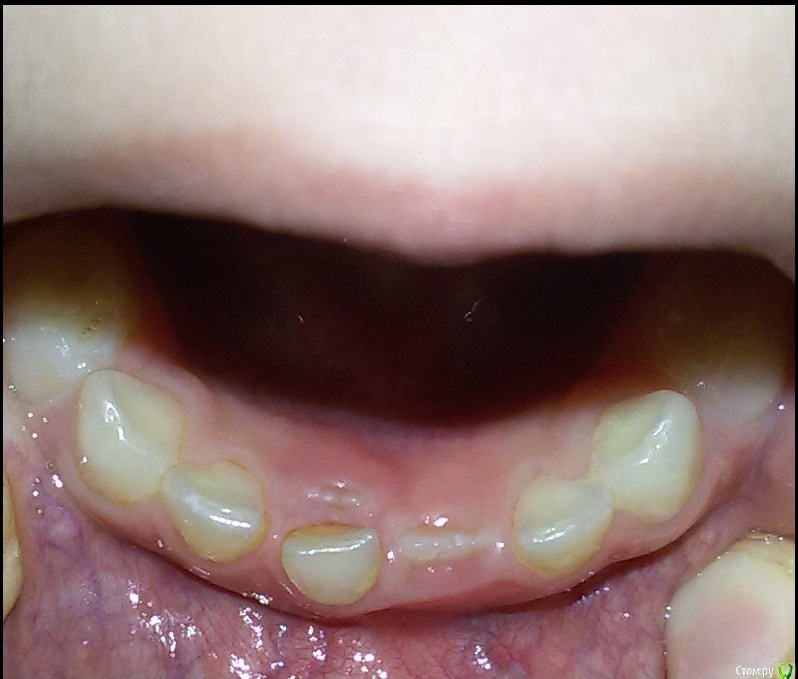

Alina93 Опубликовано 14 марта, 2017 Поделиться Опубликовано 14 марта, 2017 Здравствуйте! Дочке 7 лет, недавно выпал первый нижний молочный зуб. Второй уже шатается. Обратили внимание что под шатающимся зубом начинает расти неправильно коренной. Подскажите пожалуйста нужно ли обращаться к стоматологу и принимать какие то меры или зубик сам выправится? PS. выпал и второй Ссылка на комментарий

Brigita Опубликовано 14 марта, 2017 Поделиться Опубликовано 14 марта, 2017 Ничего страшного, пусть растет. Нижние резцы - единственные из всех зубов, встают на место в 95% случаев сами)))Молочный сам выпадет Ссылка на комментарий

red_butler Опубликовано 14 марта, 2017 Поделиться Опубликовано 14 марта, 2017 Гигиена «хрома»... Ссылка на комментарий